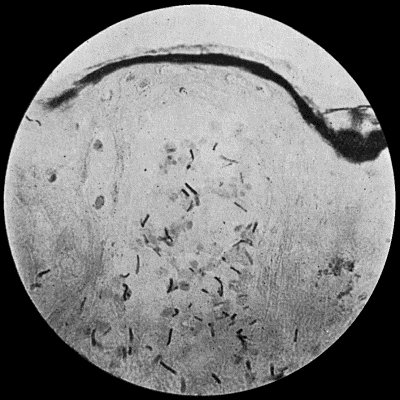

Fig. 2.—Staphylococcus aureus in Pus from case of Osteomyelitis. × 1000 diam. Gram's stain.

Staphylococcus Aureus.—This is the commonest organism found in localised inflammatory and suppurative conditions. It varies greatly in its virulence, and is found in such widely different conditions as skin pustules, boils, carbuncles, and some acute inflammations of bone. As seen by the microscope it occurs in grape-like clusters, fission of the individual cells taking place irregularly (Fig. 2). When grown in artificial media, the colonies assume an orange-yellow colour—hence the name aureus. It is of high vitality and resists more prolonged exposure to high temperatures than most non-sporing bacteria. It is capable of lying latent in the tissues for long periods, for example, in the marrow of long bones, and of again becoming active and causing a fresh outbreak of suppuration. This organism is widely distributed: it is found on the skin, in the mouth, and in other situations in the body, and as it is present in the dust of the air and on all objects upon which dust has settled, it is a continual source of infection unless means are taken to exclude it from wounds.